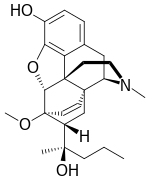

The pharmacodynamic response to an opioid depends upon the receptor to which it binds, its affinity for that receptor, and whether the opioid is an agonist or an antagonist. For example, the supraspinal analgesic properties of the opioid agonist morphine are mediated by activation of the μ1 receptor; respiratory depression and physical dependence by the μ2 receptor; and sedation and spinal analgesia by the κ receptor. Each group of opioid receptors elicits a distinct set of neurological responses, with the receptor subtypes (such as μ1 and μ2 for example) providing even more [measurably] specific responses. Unique to each opioid is its distinct binding affinity to the various classes of opioid receptors (e.g. the μ, κ, and δ opioid receptors are activated at different magnitudes according to the specific receptor binding affinities of the opioid). For example, the opiate alkaloid morphine exhibits high-affinity binding to the μ-opioid receptor, while ketazocine exhibits high affinity to ĸ receptors. It is this combinatorial mechanism that allows for such a wide class of opioids and molecular designs to exist, each with its own unique effect profile. Their individual molecular structure is also responsible for their different duration of action, whereby metabolic breakdown (such as N-dealkylation) is responsible for opioid metabolism.

Several semi-synthetic opioids were developed in Germany in the 1910s. The first, oxymorphone, was synthesized from thebaine, an opioid alkaloid in opium poppies, in 1914.[228] Next, Martin Freund and Edmund Speyer developed oxycodone, also from thebaine, at the University of Frankfurt in 1916.[229] In 1920, hydrocodone was prepared by Carl Mannich and Helene Löwenheim, deriving it from codeine. In 1924, hydromorphone was synthesized by adding hydrogen to morphine. Etorphine was synthesized in 1960, from the oripavine in opium poppy straw. Buprenorphine was discovered in 1972.[228]